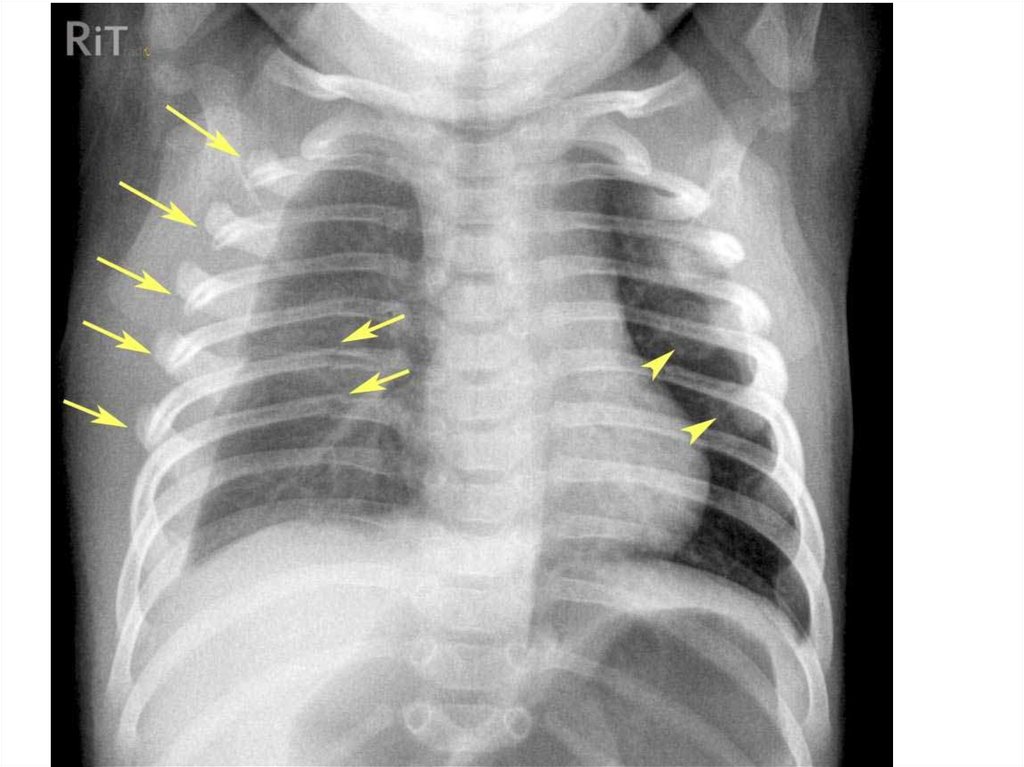

Эмфизема